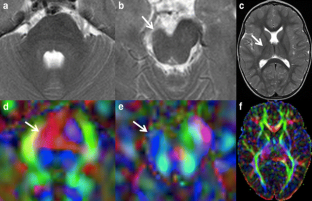

Diffusion tensor imaging (DTI) is an advanced MR technique that provides qualitative and quantitative information about the micro-architecture of white matter. DTI and its post-processing tool fiber tractography (FT) have been increasingly used in the last decade to investigate the microstructural neuroarchitecture of brain malformations. This article aims to review the use of DTI and FT in the evaluation of a variety of common, well-described brain malformations, in particular by pointing out the additional information that DTI and FT renders compared with conventional MR sequences. In addition, the relevant existing literature is summarized.